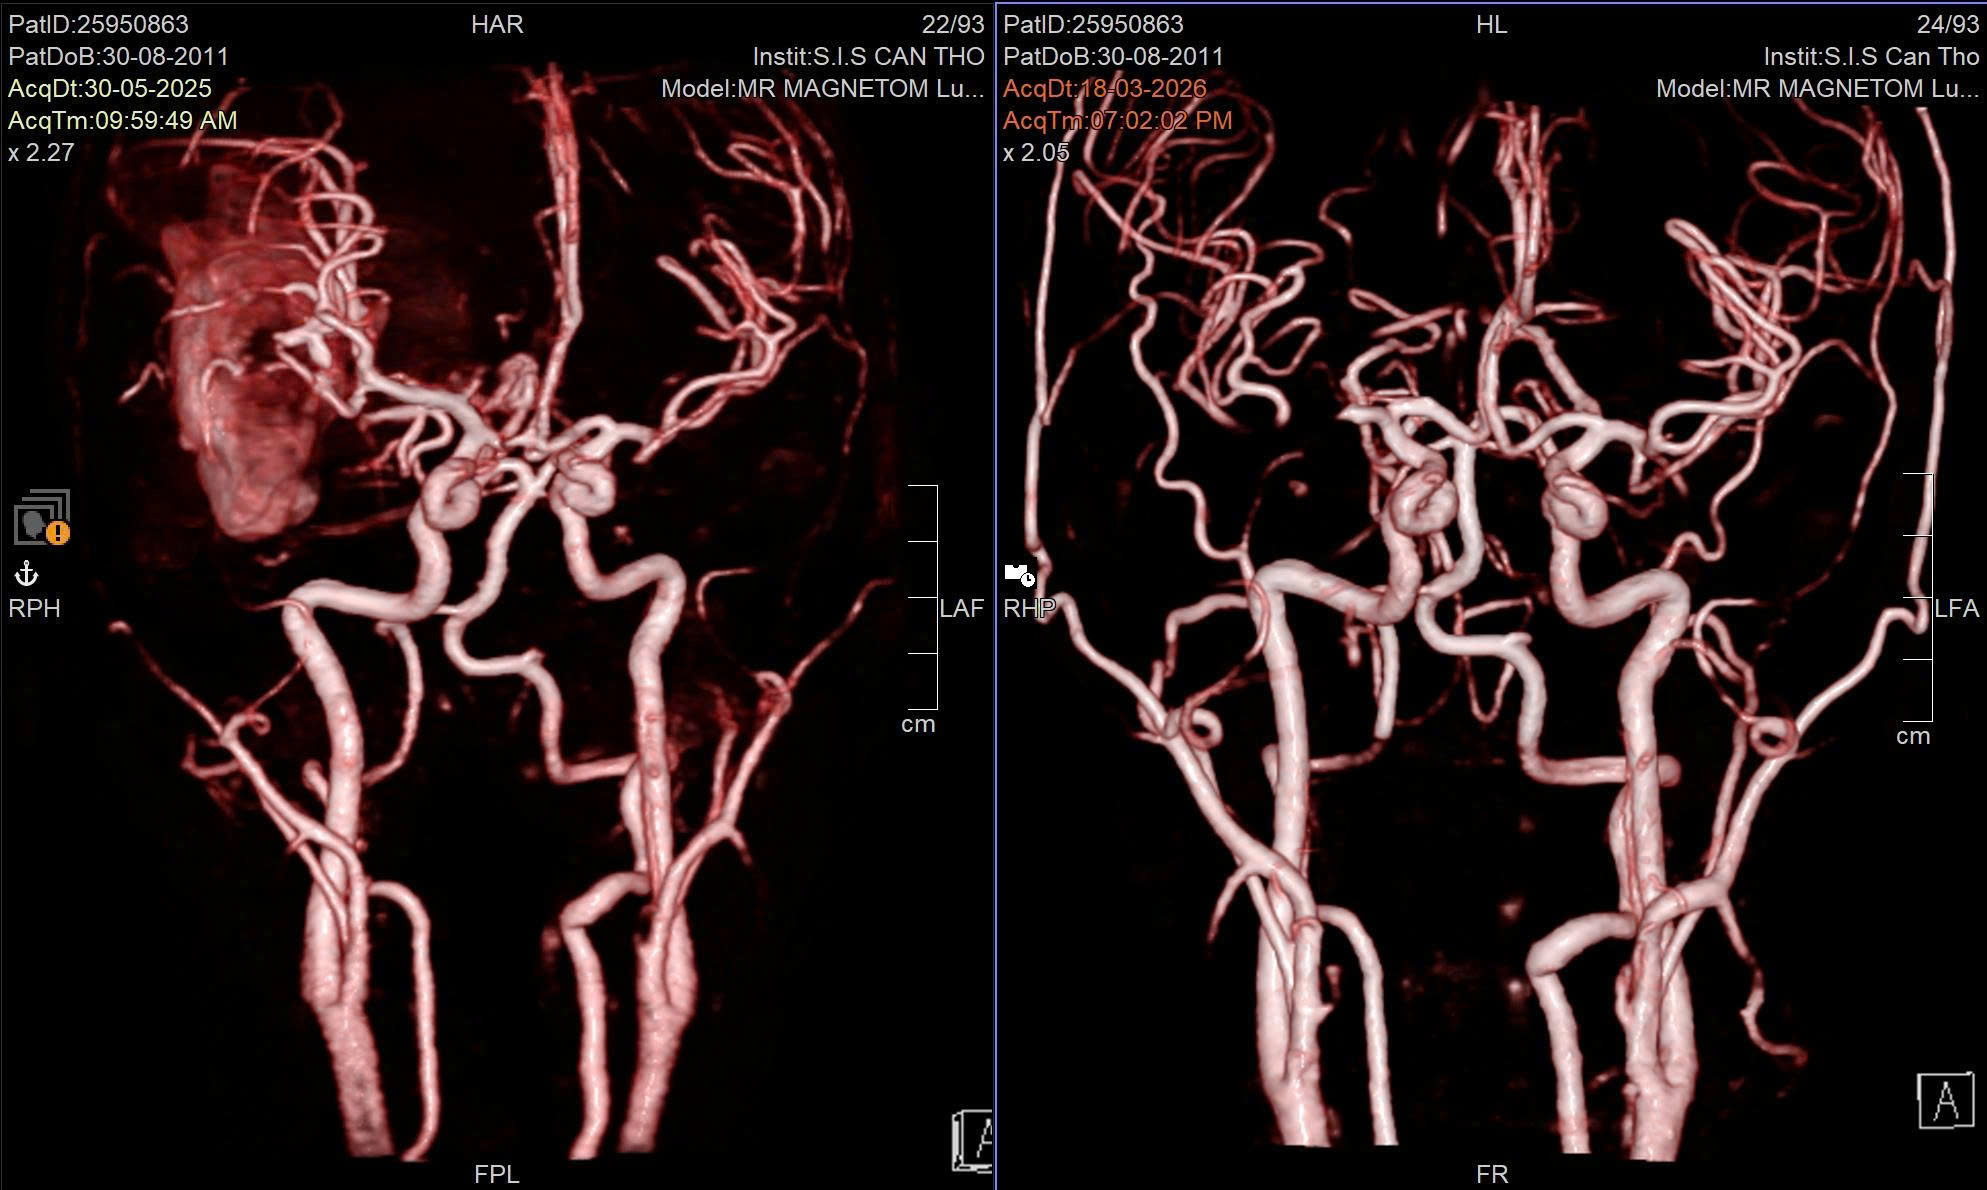

Hình ảnh kỹ thuật cao thể hiện tình trạng nguy kịch của nam sinh lớp 8.

Tại đây, các bác sĩ đã nhanh chóng chẩn đoán bệnh nhi bị xuất huyết não do vỡ dị dạng mạch máu não (AVM) – một bệnh lý bẩm sinh nguy hiểm, có thể diễn tiến âm thầm nhưng có khả năng gây tử vong trong thời gian ngắn khi bị vỡ.

BS.CKI Nguyễn Quang Hưng – Trưởng Đơn vị Phẫu thuật Thần kinh cho biết, bệnh nhi gặp phải dị dạng mạch máu phức tạp cùng khối máu tụ lớn, vì vậy, ê-kíp đã quyết định áp dụng chiến lược điều trị phối hợp.

“Bệnh nhân đã được can thiệp nội mạch nhằm giảm lưu lượng dòng chảy, hạn chế chảy máu, sau đó tiến hành phẫu thuật bóc tách và loại bỏ hoàn toàn khối dị dạng” – BS Hưng thông tin thêm.